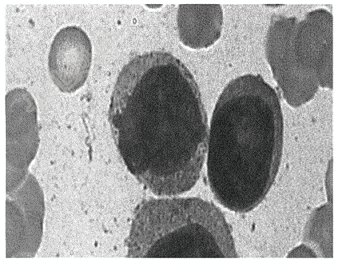

- 单项选择题患者男,56岁。其骨髓穿刺涂片如图所示,该患者最可能的诊断是( )

A、急性单核细胞白血病

B、红白血病

C、急性淋巴细胞白血病

D、急性早幼粒细胞白血病

E、急性粒细胞白血病